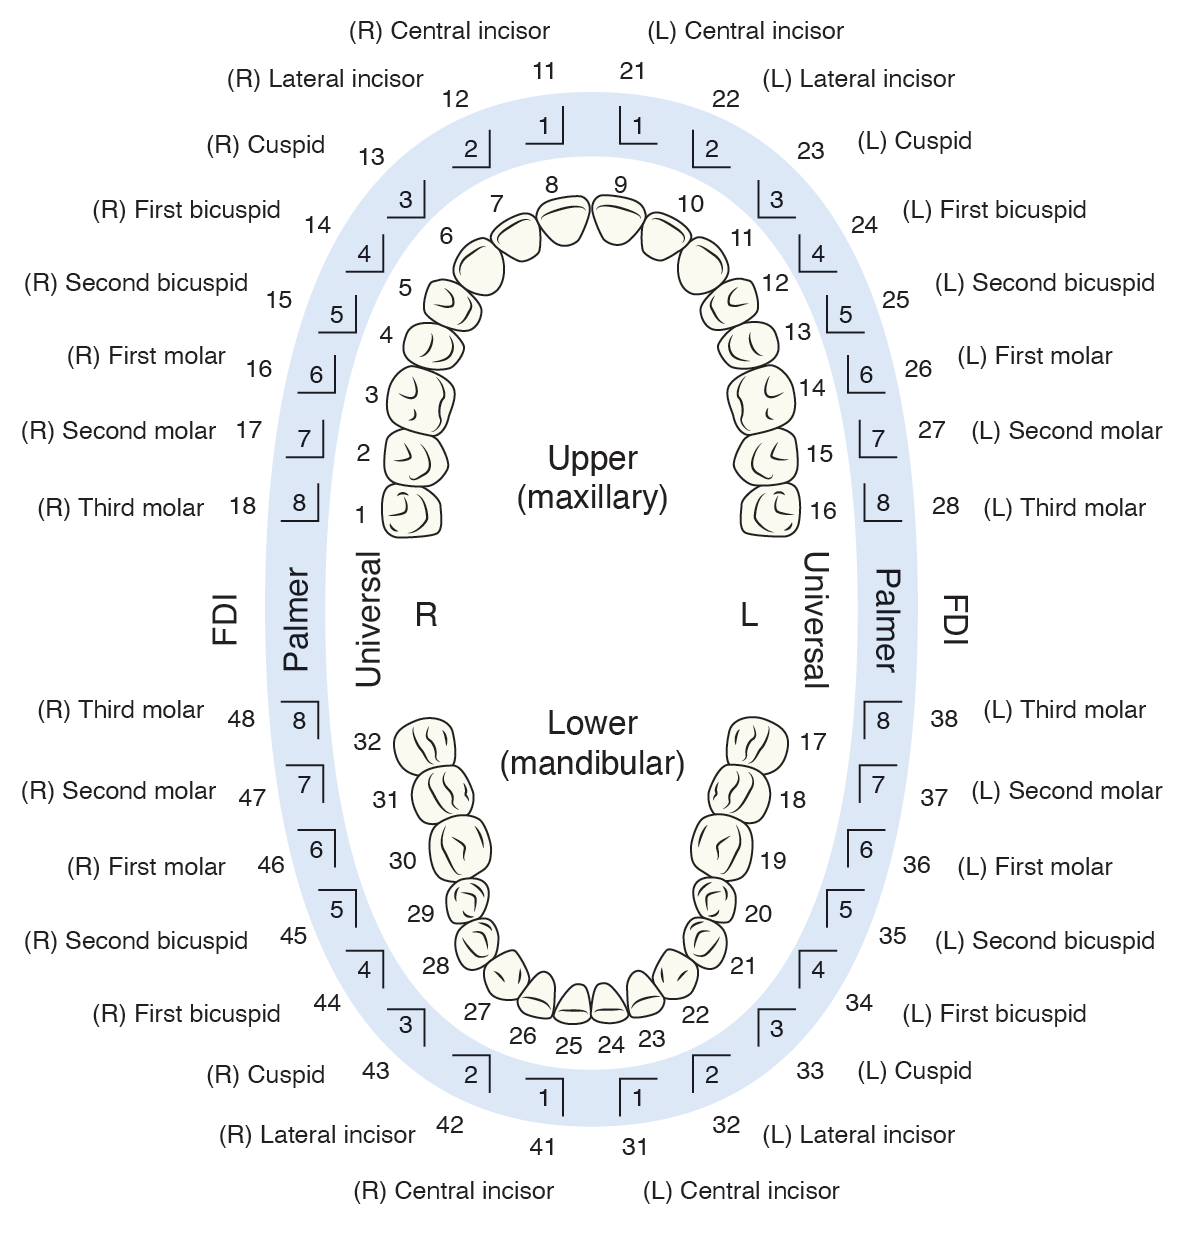

Medical Illustration

All images are works made for hire and are the exclusive property of the client. These are shown as sample purposes of my work only. For licensable work, please see my Illustration Services page.

Medical Illustrator for Precision Graphics, Lachina, and Human Kinetics Publishing (current)

Contract freelancer for many others, some examples of my work below.